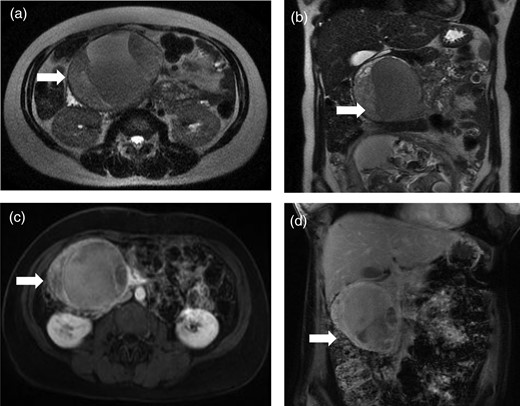

A 39-year-old woman underwent a routine fetal ultrasound in the 18th week of pregnancy, and a large solid and cystic mass in the region of the pancreas was seen. Non-contrast magnetic resonance imaging (MRI) revealed an 11.2 cm × 10 cm solid and cystic mass in the head of the pancreas (Fig. 1a and b), which was felt to be consistent with an SPN. Monthly abdominal ultrasonography revealed no growth of the mass. The patient did not experience abdominal pain, nausea or vomiting. At 40 weeks and 2 days, the mother had an uncomplicated spontaneous vaginal delivery of a healthy baby boy.

Magnetic resonance images reveal a well-circumscribed solid and cystic mass in the region of the pancreas head. Antepartum, non-contrast images in axial (a) and coronal (b) views. Postpartum, contrast-enhanced images in axial (c) and coronal (d) views.

Eight weeks after delivery, MRI with gadolinium showed a 9.3 cm × 6.8 cm solid and cystic mass in the head of the pancreas (Fig. 1c and d). There was no biliary or pancreatic duct dilatation. Major blood vessels appeared uninvolved.